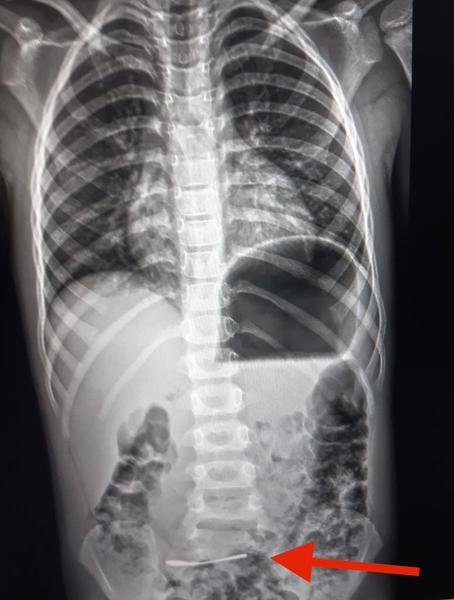

В Харькове ребенок шести лет проглотил серебряную ложку. Родители сразу же сообщили об инциденте.

Ребенка привезли в медицинское учреждение, где его обследовали врачи и на рентгене увидели в кишечнике ребенка инородный предмет.

Операции не потребовалось, ложка вышла из организма малыша естественным путем.